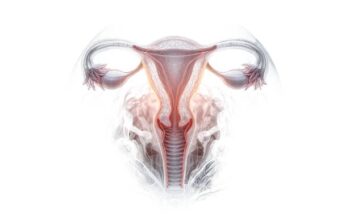

Discover the wonders of the human body, from its fundamental elements to the intricate systems that sustain life. This section explores the anatomy, physiology, and functions of various body parts, providing insights into our movements, thoughts, emotions, and interactions with our surroundings.